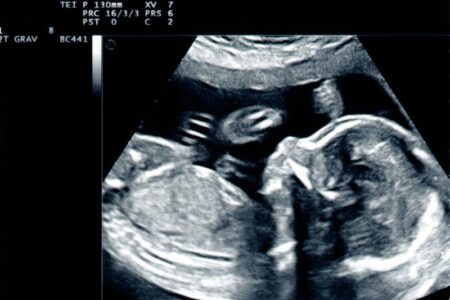

Dlaczego niedokrwistość w ciąży jest tak powszechna i jakie są jej przyczyny? Wędrując przez meandry ciąży, z pewnością napotykasz wiele emocji i doświadczeń, które potrafią zarówno zachwycić, jak i zaskoczyć. Jednym z nieoczekiwanych gości, który niejednokrotnie pojawia się na tej drodze, jest niedokrwistość. Dlaczego tak się dzieje? Gdy przyglądamy się z bliska matczynemu organizmowi, odkrywamy, …